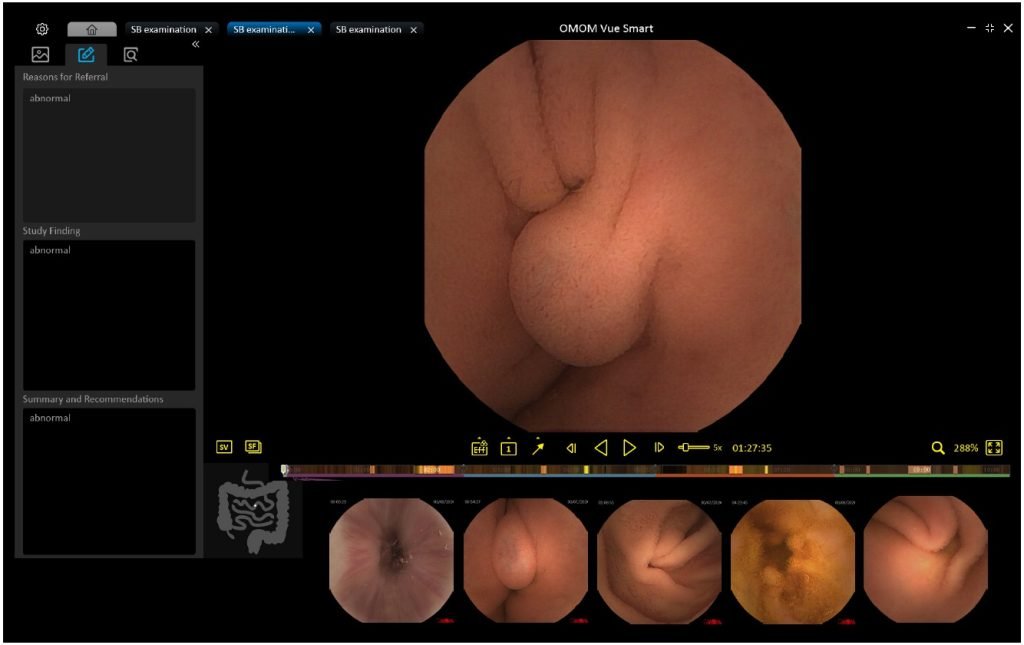

VueSmart čitanje ne može biti lakše

Uz veliku nadogradnju centra za upravljanje pacijentima i ekrana za čitanje, novi Vue Smart softver pruža zdravstvenim radnicima još jednostavniji interfejs i iskustvo čitanja bez stresa.

Sa našim naprednim AI algoritmima, Vue Smart je na novoj tehnološkoj granici u funkcionalnosti brisanja, otkrivanje lezija i klasifikacija koja garantuje lakšu nego ikada interpretaciju kao i poboljšani klinički ishodi.

Koristeći naše algoritme, SmartScan obrađuje neobrađene datoteke brisanjem do 90% snimka, identifikujući i označavajući čak 16 vrsta abnormalnosti. Nakon Smartscaning-a, SmartView i SmartFinding su spremni za upotrebu.

Režim čitanja SmartView će reprodukovati samo slike koje je pokupio Smartscan, pomažući korisnicima u tome brzo kretanje kroz ceo video. Istaknute oznake iznad vremenske trake prikazuju slike koji se može prikazati kao kratak video.

Snimanjem najistaknutijih karakteristika odabranih slika sa prediktivnim rezultatima, SmartFinding pomaže lekarima tako što prikazuje abnormalnosti i predlaže opise. Slike se prikazuju kao prikaz stranice.